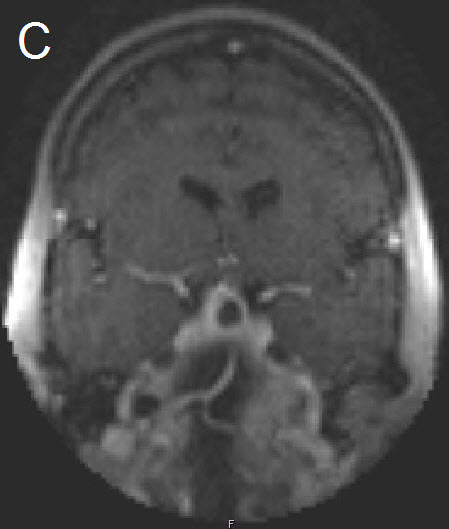

Figure 1 Illustrative case: Preoperative, intraoperative and postoperative imaging. A: Preoperative MRI, coronal view, contrast enhanced. B: Intraoperative MRI, coronal view, contrast enhanced, before skin incision. C: Intraoperative MRI, coronal view, contrast enhanced, during resection. D: Intraoperative MRI, coronal view, contrast enhanced, before closure. E: Postoperative MRI, coronal view, contrast enhanced.

A forty-two year old female was admitted for resection of a large pituitary adenoma. She complained about headache, amenorrhea and galactorrhea. Endocrinological diagnosis revealed a panhypopituitarism. The patient underwent surgery and the non-functioning pituitary adenoma could be totally removed. Postoperative follow-up showed normal pituitary function and the patient has now been in remission for 48 months. The figures show preoperative imaging, intraoperative imaging with various stages of the tumour resection, and postoperative follow-up MRI.